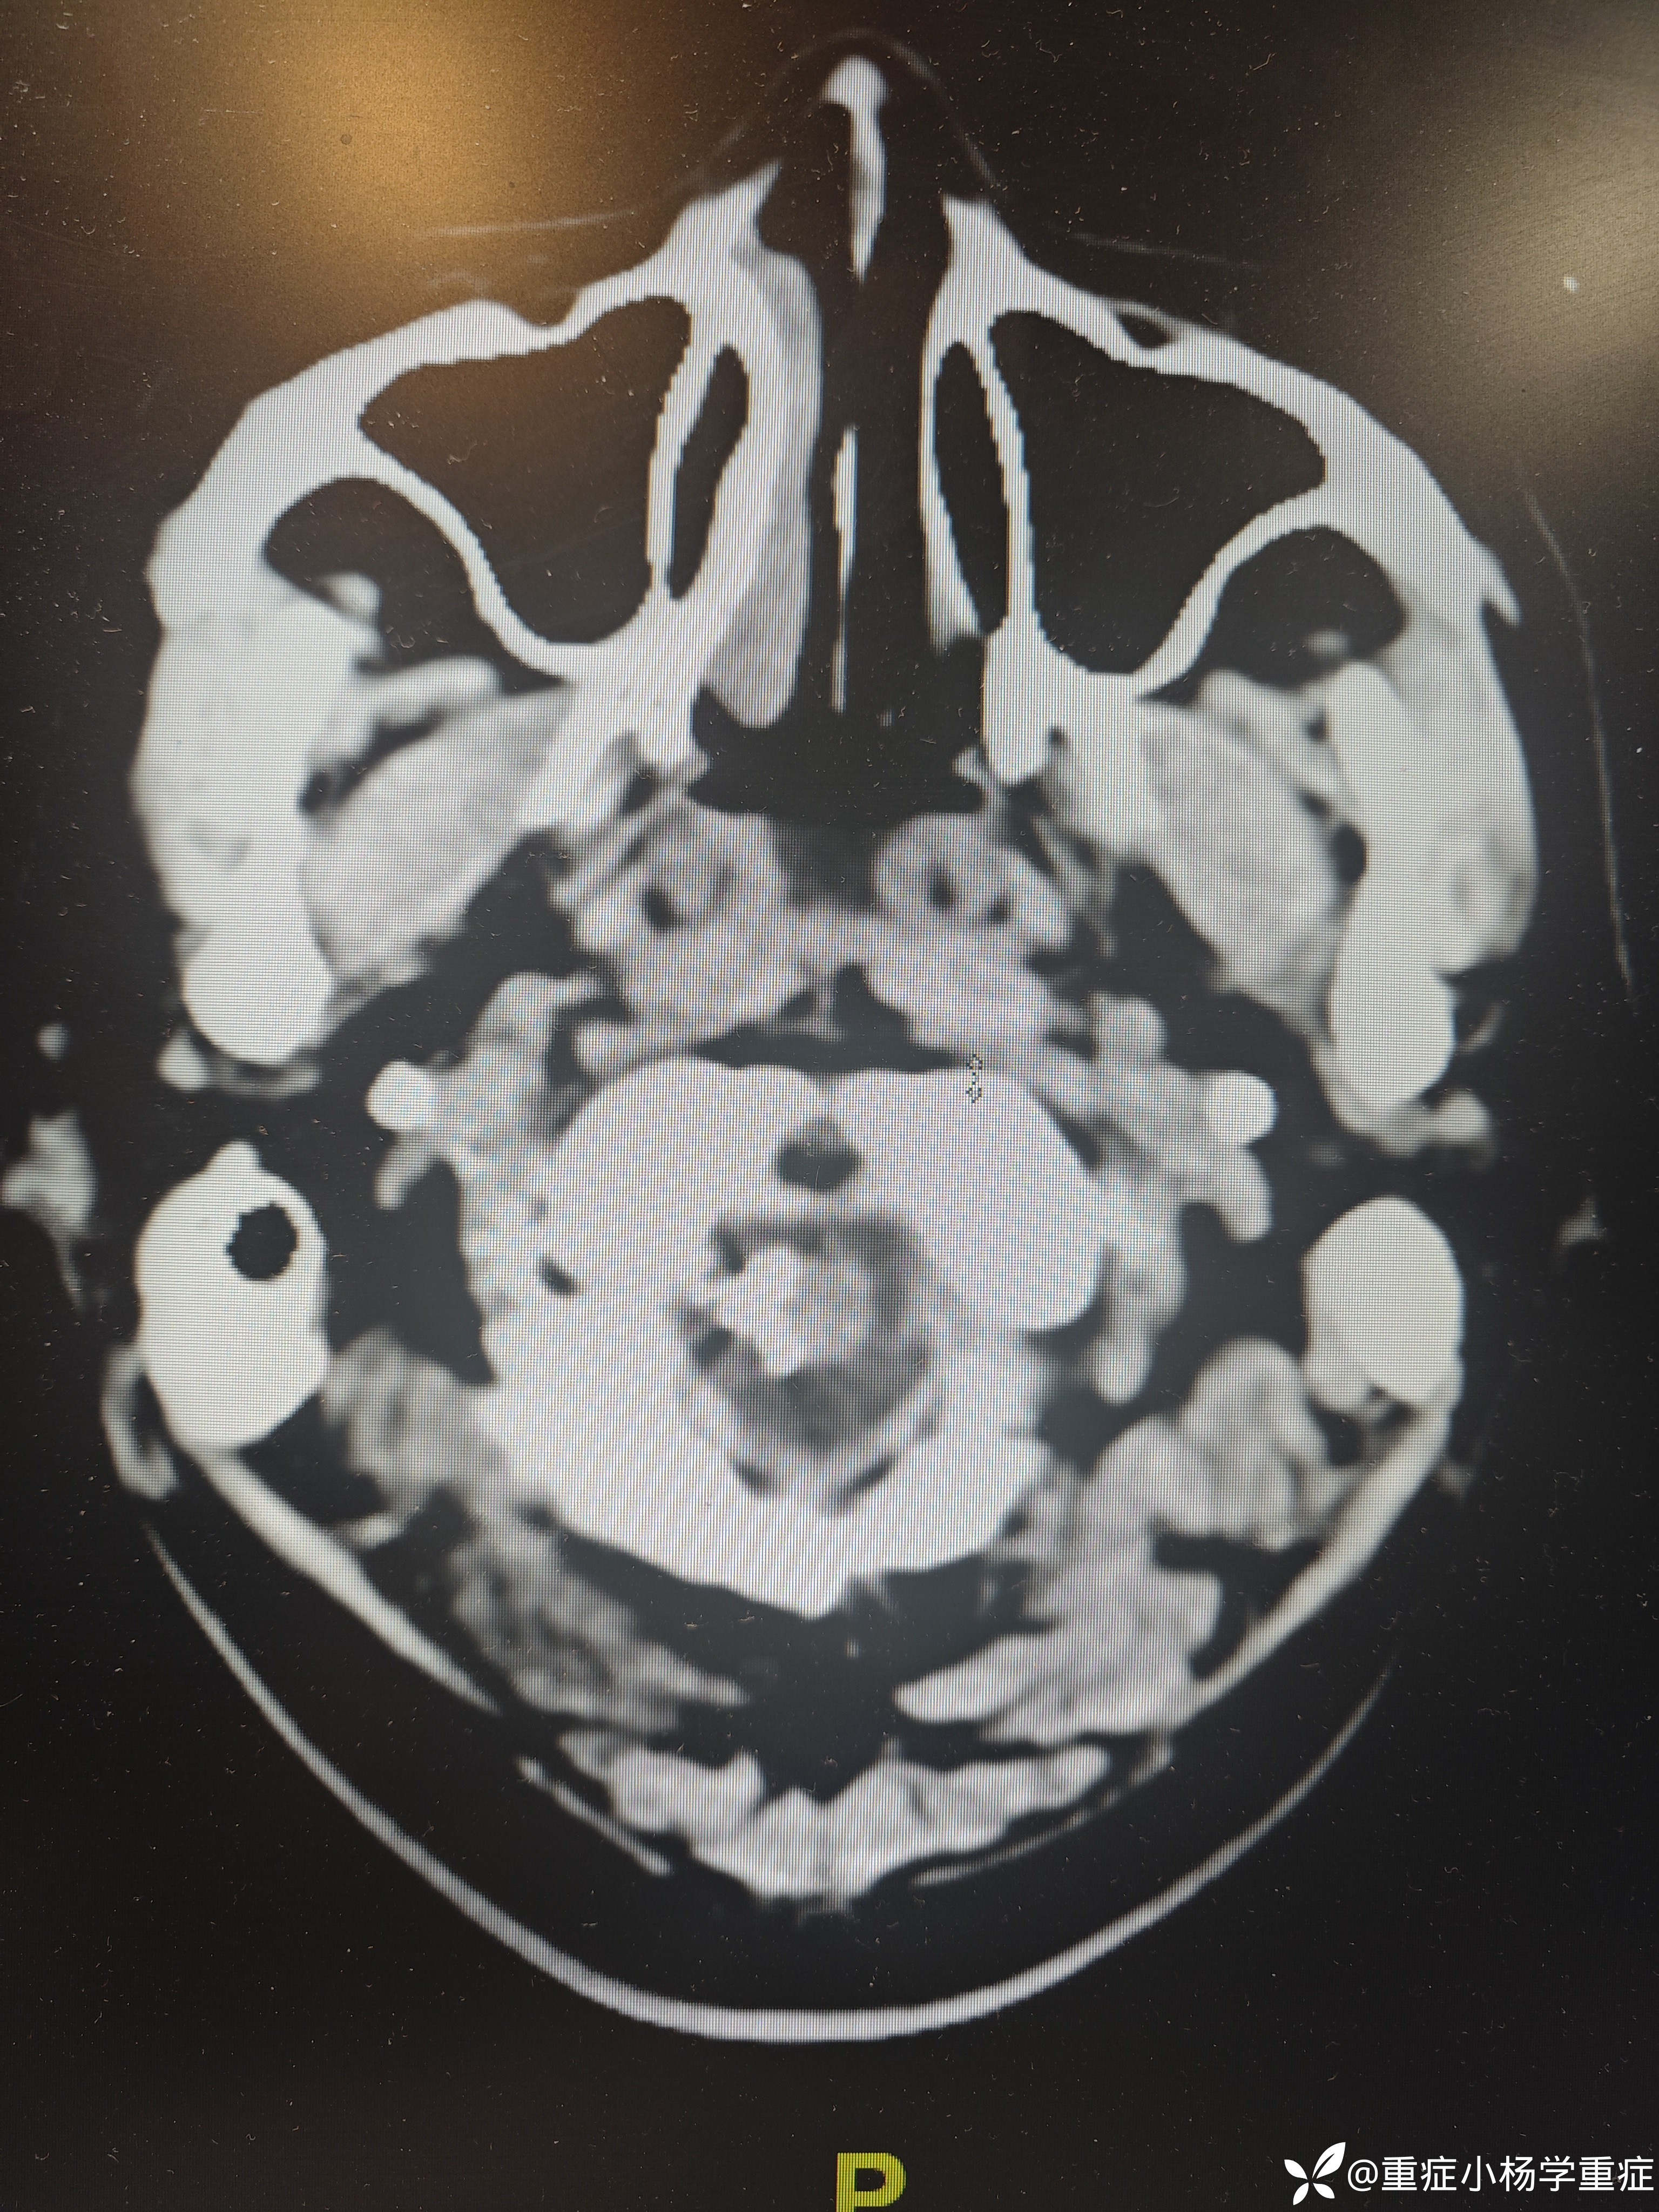

飞跃迷雾1 达人已点赞因“代:脑出血术后2月余,痰多伴呼吸困难1小时”入院。因头痛至医院检查ct提示蛛网膜下腔出血,后完善CTA提示脑血管畸形,至省内医院行介入栓塞后出现脑梗塞,考虑压迫延髓导致呼吸功能损伤,术后第二天予以气切,后出现四肢瘫痪,近期ct如下